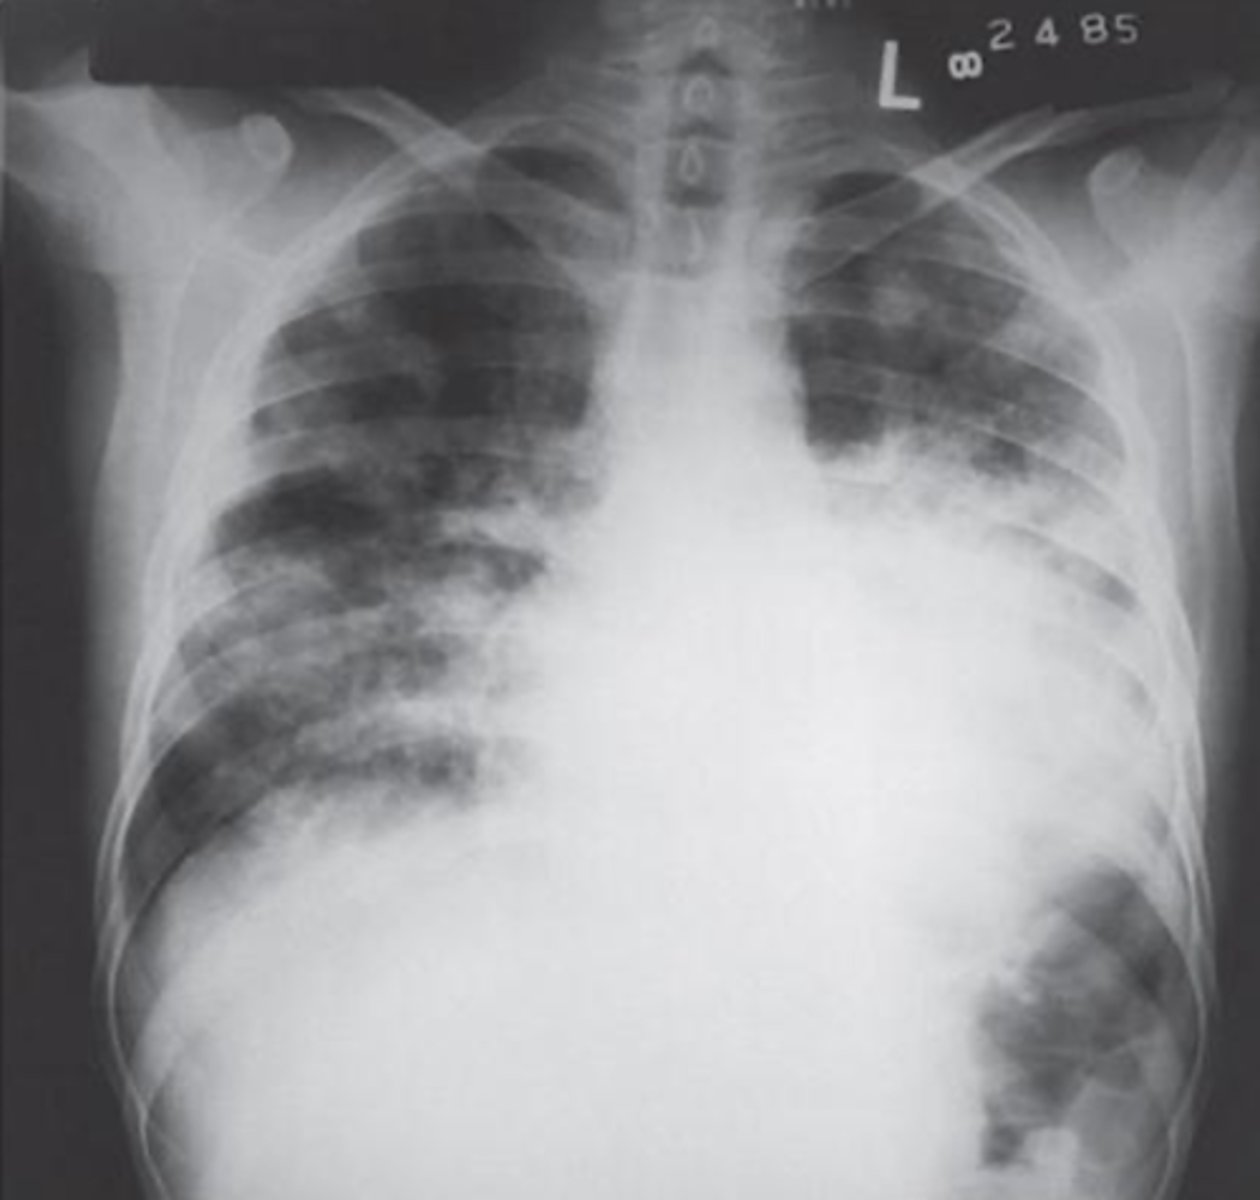

What is the pathology in this image?

Multiple myeloma

What is the pathology: cell proliferation as a result of abnormally large amount of immunoglobulin?

destructive

Is Multiple myeloma an additive or destructive (subtractive) pathology?